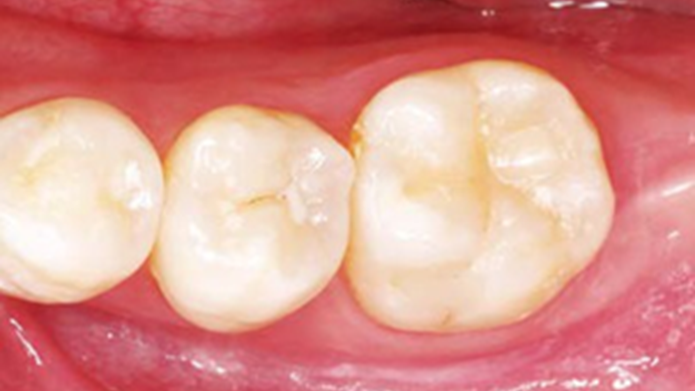

Clinical case: Bone growth in deepest thread of 8.0mm AnyRidge fixture

- Courtesy of Dr. Kwang Bum Park -

Clinical case: Bone filling into the bottom of deepest thread at 8.0mm AnyRidge fixture

Keywords

AnyRidge, Knifethread ,extraction socket, ,initial stability ,Allograft, ,osseointegratio ,Dr. Kwang Bum Park, , Mandibular, Single replacement, AnyRidge, Mega-oss,

Products used

Implant system-AnyRidge, Regeneration-Mega-Oss